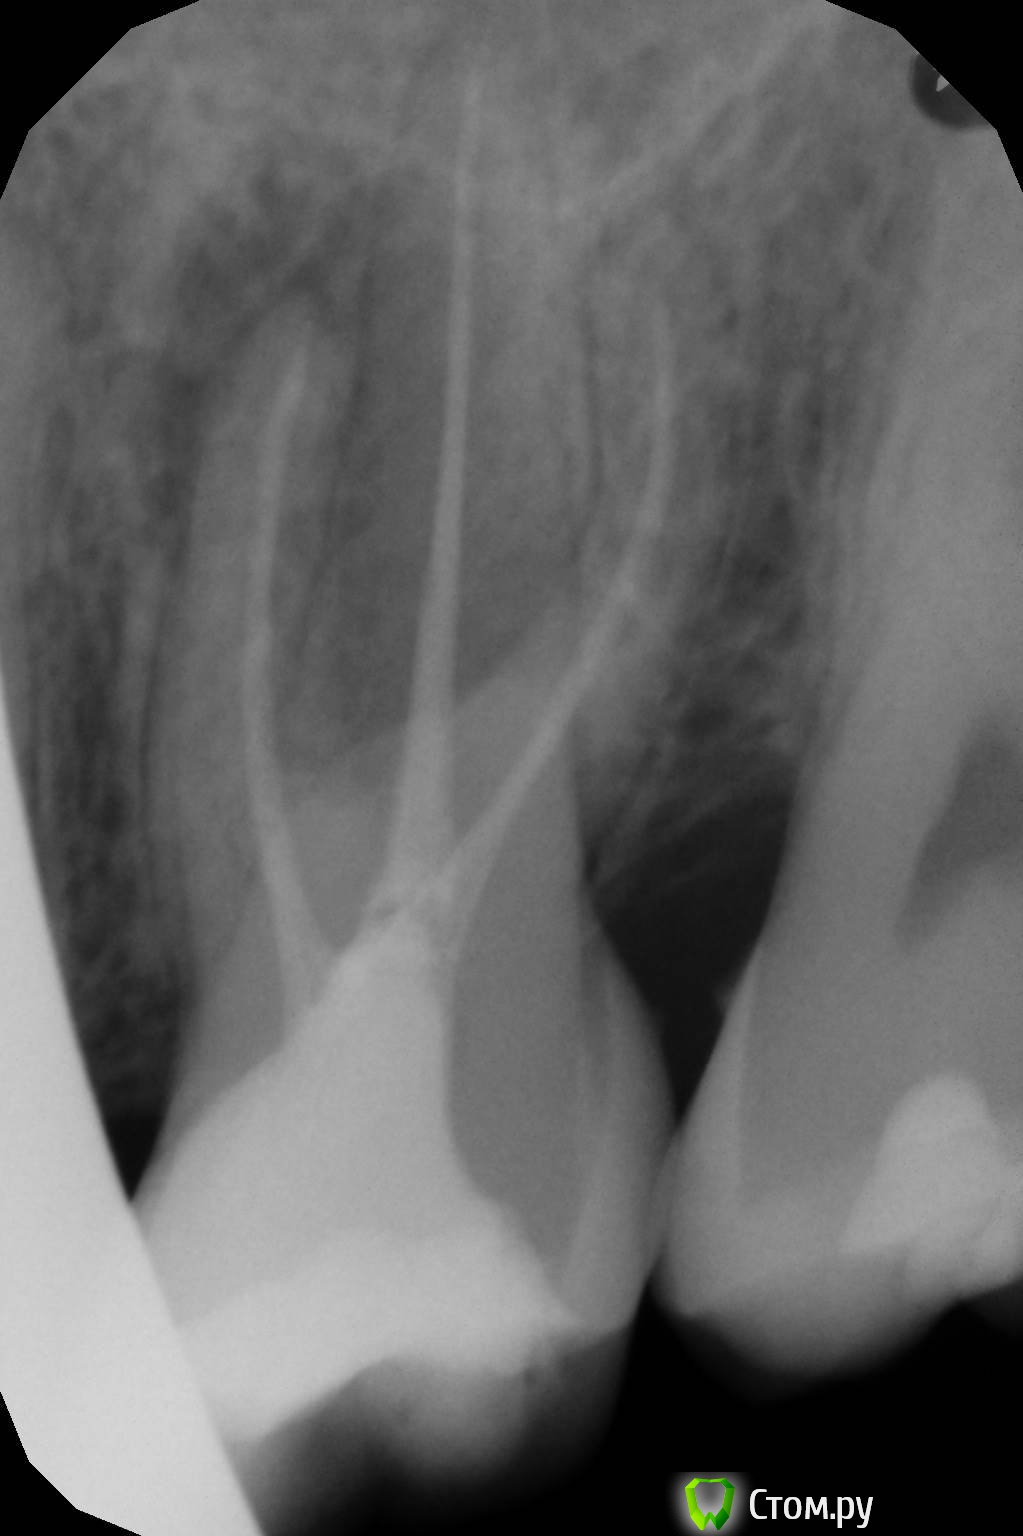

oksanab Опубликовано 2 октября, 2014 Поделиться Опубликовано 2 октября, 2014 (изменено) Консультировалась уже с 4-мя ортопедами, при чем кандидатами мед. наук, и они как-то расходятся во мнении. История такая: 12 лет назад зуб депульпировали, лет через 6 я стала ощущать дискомфорт, и на снимке было воспаление. (снимок 1). А теперь 1,5 месяца назад воспалились немного десна и через какое-то время появился флюс. Вскрыть десну я побоялась и пропила антибиотики. Флюс сошел, но десна еще оставалась припухлой слегка. Я после этого, то есть после антибиотиков, пришла к ортопеду, он начал лечить каналы 26-го зуба, и дискомфорт в десне на половину уменьшился, то есть явно стало получше. В этом зубе так же был обнаружен кариес, но врач сказал, что после лечения каналов удалит кариес, может за стенки боялся). Но во время лечения, когда стояла лечебная паста, на отдыхе зуб сломался об косточку оливки(стояла временная пломба с пастой лечебной). Ортопед через 20 дней убрал лекарство и запломбировал каналы эндометазоном(про гутаперч ничего в выписке не пишет, только это). Когда пломбировал, просил у медсестры что-то 40-е или хотя бы 38-е, у них не оказалось(может штифты...). Уж не знаю чем они там обошлись, но меня такая клиника напрягла. Врач поставил временную пломбу, удалил кстати, отломавшийся кусочек зуба, и сказал приходить через 3 дня, чтобы удалить кариес в этом зубе и смотреть его устойчивость, чтобы определиться с коронкой или вкладкой. Поскольку в этой клинике вечно чего то нет, я перешла в другую. Пришла к кандидату мед. н аук с 25 летним стажем. Он заявил, что скорее всего нужна резекция корня зуба, и отправил меня в институт научно-исследовательский(ЦНИИС и ЧЛХ). Так я попала к следующему к.м.н.- ортопеду Мурадову. Этот радостно сообщил ,что все замечательно, резекции не надо. Но он пропустил кстати перфорацию корня у дистально щечного канала , как и первый к.м.н., он тоже пропустил ее,( его только воспаление у десны обеспокоило, поэтому отправил в институт на консультацию в институт.) А вот уже в институте второго ортопеда -к.м.н. -Мурадова, ничего по десне не обеспокоило, сказал будем ставить коронку. Пока ждала 2 недели очередь , так уж получилось, что я сходила еще к одному ортопеду, чтобы заменил временную пломбу. Он посмотрел снимок, и он первый из врачей, кто вообще заявил, что есть перфорация корня и зуб надо удалять! Однако, я вернулась все таки пошла на лечение к Мурадову ,который радостно брался за этот 26 зуб. И когда я пришла на лечение через 2 недели по его огромной записи, тут вдруг выяснилось... Он вскрыл зуб, сказал что-то про запах, сразу его запаял и заявил, что паста мягкая, надо перепломбировать. Паста - эндометазон. Я попросила повнимательнее посмотреть на снимок, и посмотреть есть ли там перфорация. Тут наконец-то перфорацию заметил и он, хотя видел снимок и две недели назад, и сегодня перед началом лечения. В итоге мне заявил, что, ну пусть терапевт разберется есть там перфорация или нет, потому что на обзорном снимке видно, что угол у зуба другой. Прилагаю три снимка(зуб до лечения, и общий снимок до лечения, и зуб после лечения и пломбировки каналов эндометазоном и уже со сколом зуба). Так вот он все-таки не совсем понял, есть ли перфорация канала. Отправилась я тогда к зам. главного врача этого института ,она оказалась тоже к.м.н. и именно ортопед. Может она конечно хотела прикрыть Мурадова, не знаю, но сказала, что хотя она не очень знает эндометазон, но тоже считает, что надо сделать перепломбировку. На мой вопрос почему врачи, да еще и к.м.н. не замечают перфорацию, ответила, что это конечно не хорошо, но и ей лично кажется, что все-таки перфорация есть. Однако ей было сложно рассмотреть мои снимки на айфоне, то есть я показывала снимки с своего телефона. Поэтому она порекомендовала мне записаться к их терапевту, чтобы внимательнее просмотрел все, может снимок сделал еще один, и чтобы перепломбировали канал методом латеральной конденсации, и пролечили перфорацию. И кстати говоря ,не рекомендовала не резекцию корня зуба, ни его удаление. По факту что у меня получается. Первый к.м.н. - за резекцию корня. Остальные три против резекции. Пятый ортопед вообще за удаление. И вот через 4-5 дней из-за очередей попаду к их терапевту какому-то толковому, тоже будет мозговать, есть ли перфорация, и чего делать то. Народ спасите. ЁПРСТ, я с этим зубом уже полтора месяца хожу, а они только трепятся, а за лечение никто еще не взялся. Только мне все истории разные рассказывают. Я уже готова и удалить его, хотя очень импланта боюсь. И готова рискнуть, поставить коронку, а если чего будет, ну резекцию тогда. Но тот врач, который сказал, что зуб надо удалять, сказал, что и резекция всего лишь временно поможет и толку в ней не будет. Блин, блин, блин... Как я простой человек могу в этом разобраться. И вообще , я больше месяца только на одну сторону жую ,это же тоже наверно не очень хорошо. Перелеченный недавно зуб на втором снимке со сколом зуба. Изменено 2 октября, 2014 пользователем oksanab Ссылка на комментарий

Cleric Опубликовано 3 октября, 2014 Поделиться Опубликовано 3 октября, 2014 (изменено) Во-первых, эндометазоном и прочими пастами уже давно не пломбируют каналы, т.к. они показывают плохие результаты в виду отстутствия герметизма, а также наличия гормонов в составе (каналы должны пломбироваться гуттаперчей на эпоксидном силере)Во-вторых, воспаление наиболее вероятно возникло из-за пропущенного 4го канала, т.е. в переднем щечном корне не 1 канал, а 2.В-третьих, многое зависит от глубины скола стенки, если глубоко под десну - то шансов на адекватную реставрацию немного.Вам необходимо найти врача стоматолога-эндодонтиста и спасти зуб от удаления и прочих к.м.нов с институтах В Москве есть много прекрасных специалистов по эндодонтии, но лечение стоит немалых денег, но оно СТОИТ того. Изменено 3 октября, 2014 пользователем Cleric 1 Ссылка на комментарий